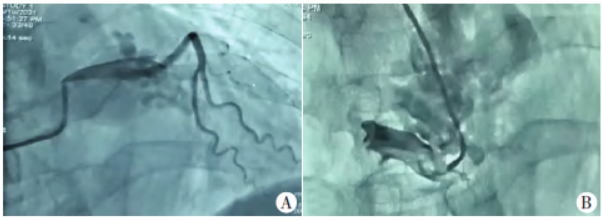

超声心动图检查:①左、右冠状动脉起始段增宽,内径分别约8 mm、7 mm,心底部、大动脉根部前方形成蜂窝状血管性团块,范围约79 mm×29 mm,冠状静脉内径约8 mm;②左房前后径45 mm,左室前后径52 mm,右房上下径、左右径分别为59 mm 、49mm,右室前后径21 mm,升主动脉内径34 mm,肺动脉内径29 mm;③彩色多普勒及频谱多普勒示心底部、大动脉根部前方蜂窝状血管性团块表现为多发、扭曲的五彩镶嵌血流,来自左、右冠状动脉,呈高速连续的动脉频谱信号。见图1。

图1 术前超声心动图检查图。A:心底部、大动脉根部前方形成蜂窝状血管性团块;B:血管性团块血流频谱显示为以收缩期为主的连续动脉频谱信号;C:右冠状动脉增宽,内径约7 mm;D:左冠状动脉增宽,内径约8 mm